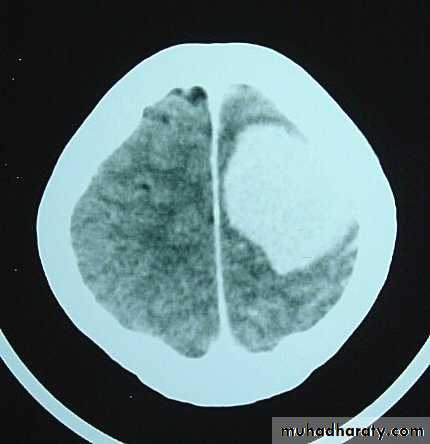

Metastatic Brain Tumours

Metastatic Brain Tumours Pre contrast CT